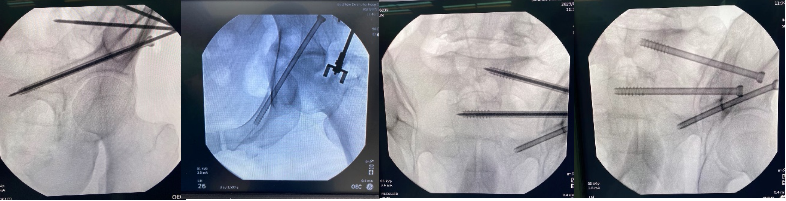

手术当天,骨科治疗组组长何罕亮副主任医师带领团队采用先进的二代臂机对患者进行骨盆图像采集,并将影像学资料上传至机器人计算机中。经过机器人的精密运算,患者的骨折三维图像非常直观地呈现在医生面前。随后,何主任团队根据图像实时进行手术规划,选择最佳置钉通道。手术机器人机械臂根据制定好的路线精准定位,将误差控制在1mm之内,使得医生不必扩大切口即可暴露骨折断端。只需3个毫米级切口,螺钉便可精准打入狭长的耻骨中,避免损伤重要的血管、神经组织。通道确定后,整个置钉过程短短几分钟便完成了,手术出血量不足10ml。精准的置钉操作使得医生不必担心反复调整所致的钉道松动,术后透视也进一步确认了螺钉位置准确无误,这预示着手术圆满成功。

机械臂手术现场